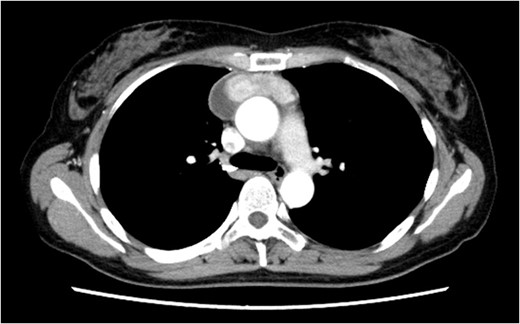

A 46-year-old woman presented to a previous hospital with an abnormal shadow on a chest X-ray. Computed tomography (CT) revealed an anterior mediastinal mass lesion with its largest diameter of 6.6 cm (Fig. 1). Therefore, she was referred to our hospital with suspicious mediastinal malignancy. All tumor markers examined were within normal limits.